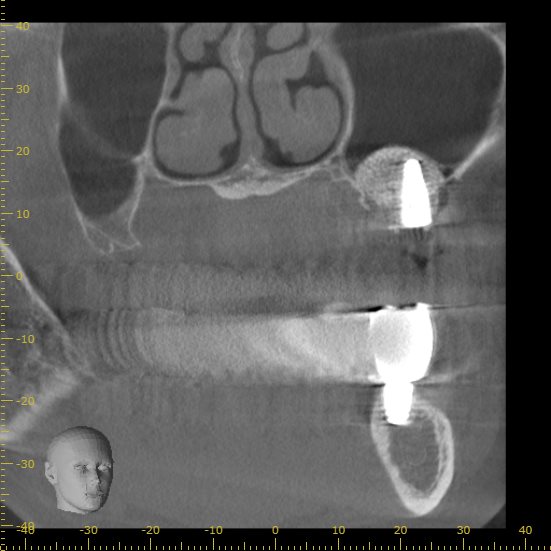

今後インプラントの処置を行い、左右で同じように噛めるよう進めていく事になりました。